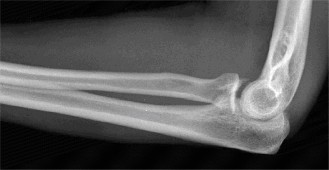

Understand common complications associated with performing surgery for scapulothoracic bursitis? CASE 33 A 42-year-old female presents to the office for follow up after sustaining a minimally displaced radial head fracture 3 months prior. She states she was initially treated in long-arm splint by the ER and did not follow up with an orthopaedic surgeon until now. Per her report, she removed the splint 4 weeks after the injury, but did not move her elbow due to pain. She now has no pain but is unable to reach that hand to her face or head. The remaining history is significant for previous ulnar nerve surgery for which she is unable to provide details. On physical examination, her upper extremity is normal except for limited flexion/extension, measured to be 80 to 50 degrees by goniometer. In addition, she has a well-healed surgical incision about the medial elbow, consistent with a previous surgery on her ulnar nerve. Her images are shown (Figs. 2–82 to 2–84).

Figure 2–82

Figure 2–83

Figure 2–84

The correct answer is (A). Classification of post-traumatic elbow stiffness allows for better understanding of the disease and allows the clinician to treat the underlying cause of the joint contracture. Intrinsic causes include: any problem within the joint such as incongruency, loose bodies, or severe osteoarthritis. Extrinsic causes include capsular tightness, muscle contracture, heterotopic ossification, and skin contractures. Early is defined as within 6 months of the injury while late is considered to be greater than 6 months after the injury. Patients that present in the early time frame have a significantly better chance at having a good result both from nonoperative and operative treatment.